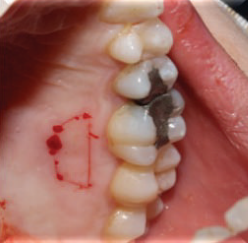

患者38岁,女,发现牙龈无痛性增生肿胀。患者未服用任何药物,未处于妊娠期,家族史无异常。

口内检查发现患者13、14牙间牙龈肿胀,质硬,无蒂,牙龈周围轻度菌斑堆积,牙龈轻度红肿。13、14牙不松动。

计划切除增生牙龈。由于增生范围较大,拟利用腭侧牙龈进行软组织修复。